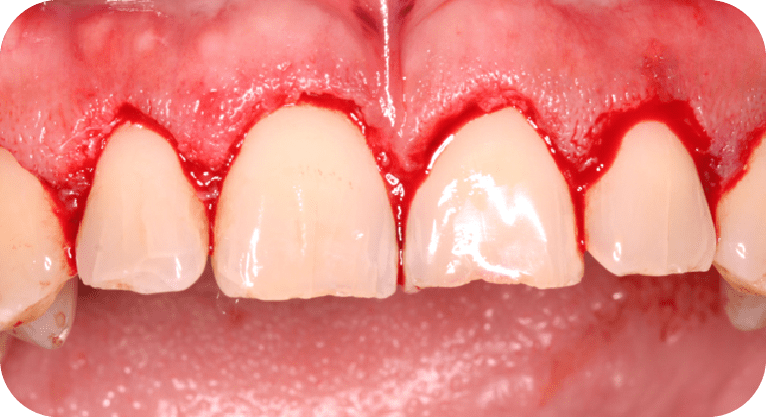

Paciente masculino, “45” años

Tratamiento: Cirugía de encías

El paciente manifestó inconformidad con el aspecto corto de sus dientes, por lo que se realizó una cirugía periodontal de remodelación gingival para recontornear el tejido gingival y exponer mayor superficie dental, logrando así una proporción dentogingival más armónica y mejorando significativamente la estética de su sonrisa.